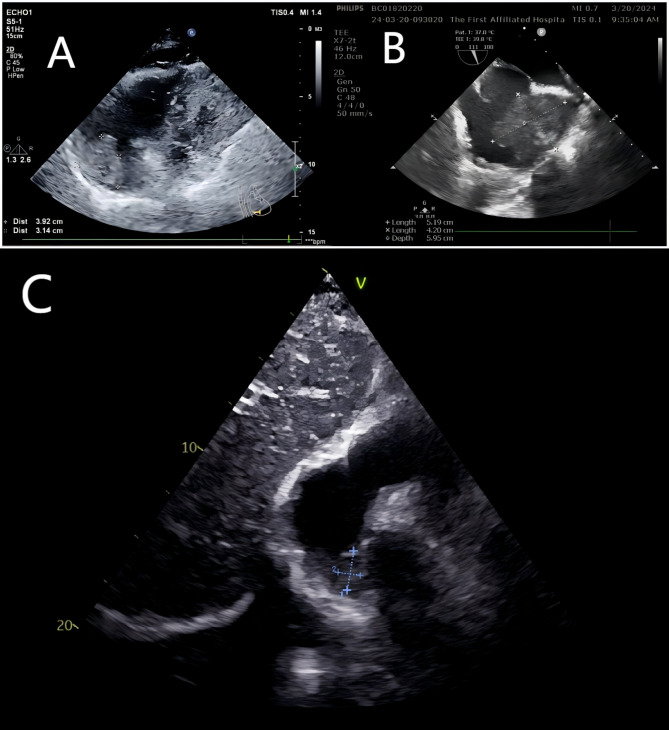

Case presentation: We report the case of a 68-year-old woman presenting with palpitations, dizziness, and obstructive cardiac symptoms. Diagnostic imaging revealed a large mass in the right atrium near the superior vena cava. A novel "zongzi"-shaped endoscopic gauze folding technique was employed to facilitate complete tumor resection while preserving cardiac structure. Pathology confirmed double expressor DLBCL with BCL2 and MYC co-expression, indicating a high-risk profile. The patient's postoperative course was uneventful, and she was discharged in stable condition. However, follow-up imaging at six months revealed local disease progression.